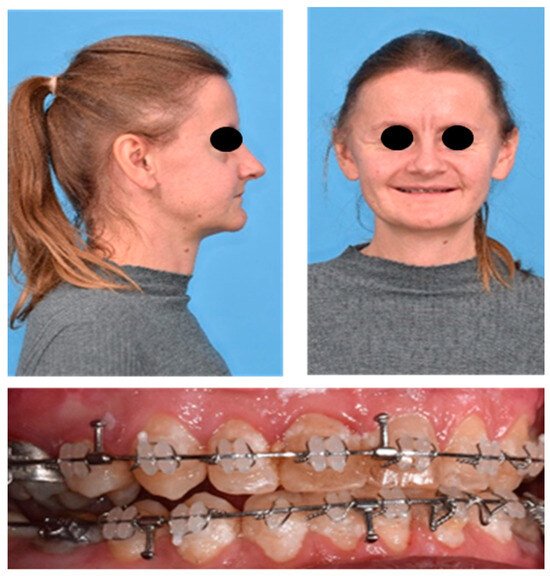

2. Case Report